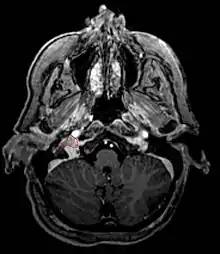

- Commonly arise from the paraganglia of the jugular bulb

- Typically invade the tympanic cavity and jugular foramen

- Can extensively invade petroclival region

- Can invade cavernous sinus above

- Can invade hypoglossal canal below